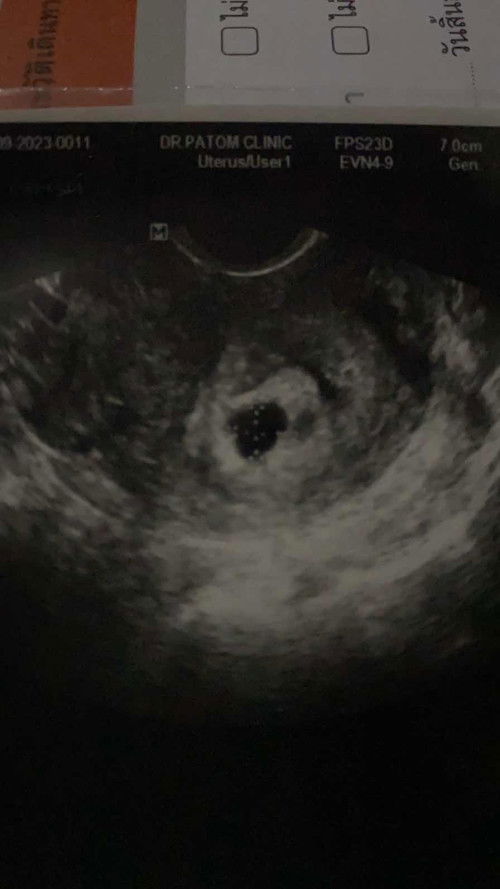

ท้องประมาณ7สับดาห์ แต่อายุครรภ์จริงๆ6สับดาห์

แม่ๆคนไหนเลยเป็นบ้างคะ ซาวครั้งแรกถ้านับตามประจำเดือนน้องจะอยู่ที่5สับดาห์ค่ะ เจอแต่ถุงเล็กมากๆ แม่กังวลมาก เพราะท้องแรกท้องลม และแท้งสมบูรณ์ค่ะ วันนี้คุณหมอนัดอัลตร้าซาว ปรากฏว่าเห็นตัวอ่อน อายุครรภ์ 6สับดาห์ มีใครเคยเป็นแบบนี้บ้างคะ แม่ๆคนไหนเป็นแบบนี้บ้างคะ#ขอบคุณสำหรับคำคอมเม้นล่วงหน้าค่ะ